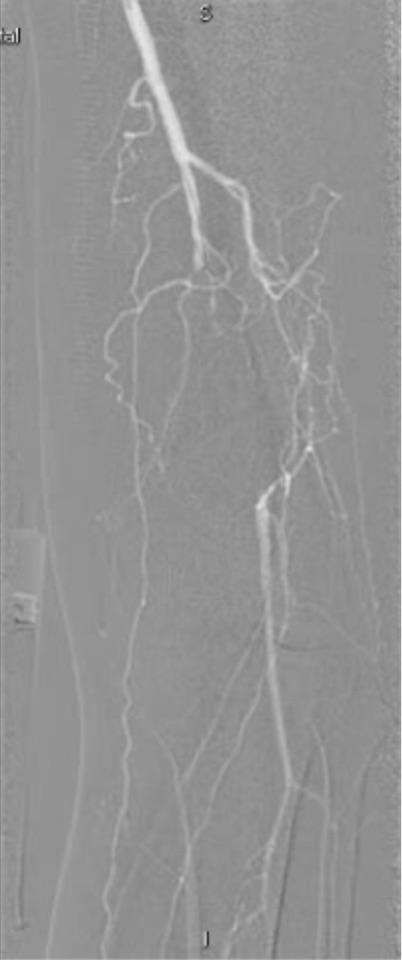

下面是术中dsa造影血管堵塞的情况

最后的结果令人满意,而且达到了患者的诉求,尽量不植入支架,来看看最后的造影结果吧